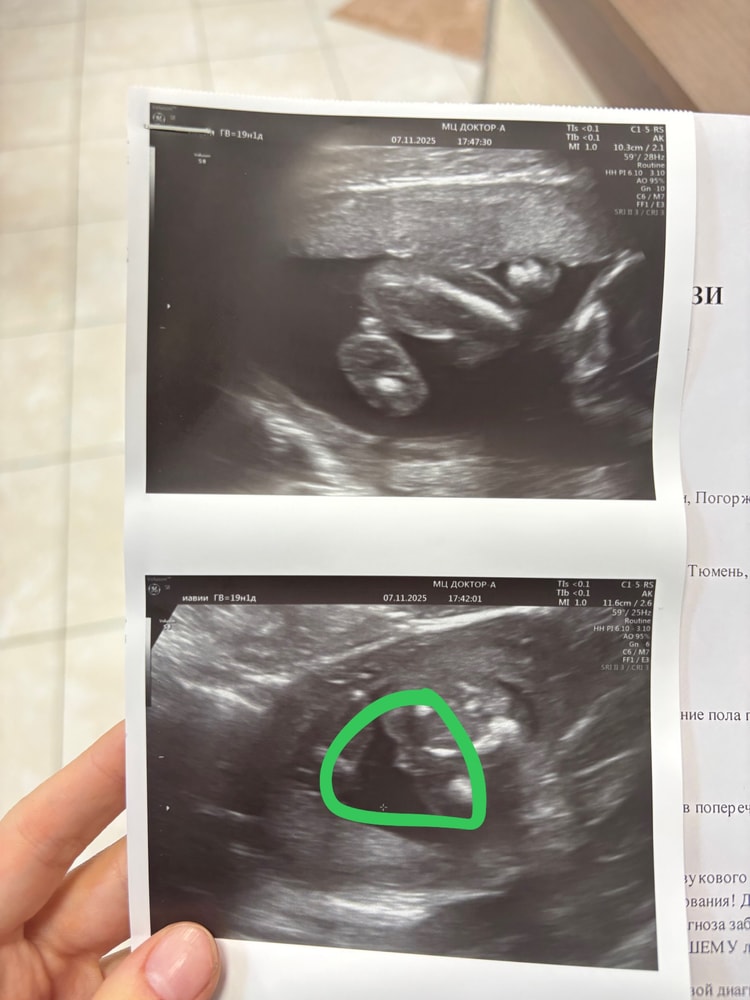

Девочки, у кого-нибудь совпало определить пол ребенка? С моими двумя старшими совпало 100%

Я никого не призываю верить в это! Это тоже самое, как гадать на ромашке. Просто у кого-то совпало, а у кого нет. УЗИ и то ошибается. Не могу понять откуда столько у людей агрессии. Вроде все девочки